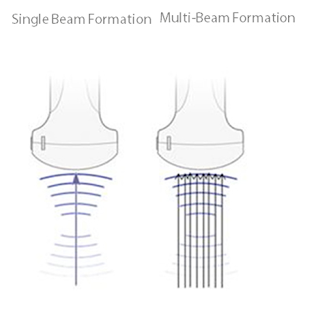

Многолучевое формирование

Увеличение скорости обработки сигнала от одного луча до восьми для получения превосходного разрешения по времени и более высокой частоты кадров.